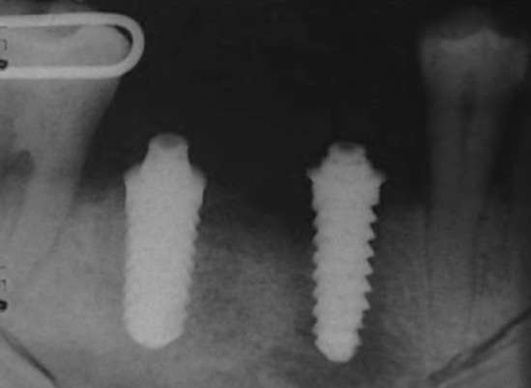

На рентгенограмме боковой проекции нижней челюсти при хроническом процессе характерна резорбция кости чаще в виде широкой щели у шейки зуба и по ходу корня, нередко в виде полулуния (рис. 14-18).

image

Рис. 14-18. Рентгенологическая картина ретенции зуба мудрости с полулунным очагом деструкции кости в проекции коронки